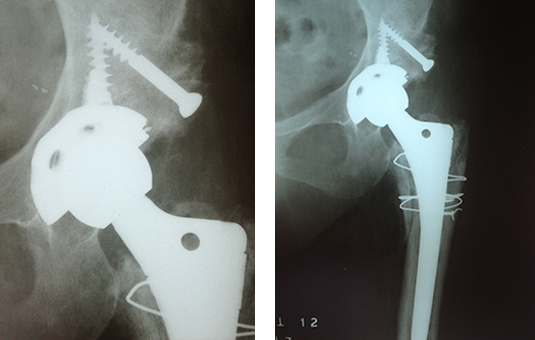

CORRECCIÓN DE AFLOJAMIENTO DE PRÓTESIS 1.PRÓTESIS AFLOJAMIENTO E INFECCIÓN DE VARIOS AÑOS. 2. RETIRO DE LA PRÓTESIS Y COLOCACIÓN DE PERLAS DE ANTIBIÓTICO ENTREVISTA PROGRAMA VIDA ENTREVISTA BDP CANAL 5 ENTREVISTA PIE PLANO ENTREVISTA ZAPATOS CORRECTOS INFILTRACIÓN DE ÁCIDO HYALURONICO EN CADERA